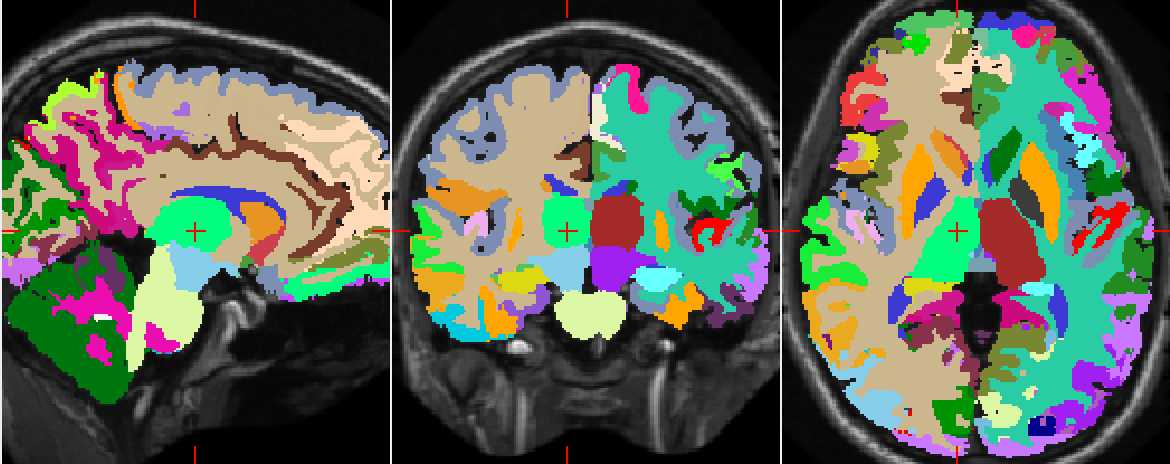

Refer to caption

(a)

(b)

(c)

Figure 6: Comparison of the automatic and manual segmentations of the cerebral white matter region (in green) of the right hemisphere of an example MRI (ID: 1004). (6(a)) Segmentation returned by the network using only the three orthogonal 2D patches as inputs, (6(b)) Manual segmentation, (6(c)) Segmentation returned by SegNet. Contrary to (6(c)), (6(a)) wrongly classifies some parts of the left hemisphere.

Figure 6 illustrates how well the downscaled patches and the distances to centroids enforce the global spatial consistency of the segmentations. Figure 7 shows the manual and automatic segmentations of a particular MRI. We notice that the misclassified voxels tend to lie on the boundaries of the regions, as expected.

(a) Manual segmentation.

(b) Predicted segmentation.

(c) Difference, white voxels are identical while blue are different.

Figure 7: Comparison of the manual brain segmentation of a subject (ID: 1004) to that predicted by SegNet. The mean dice coefficient is 0.74.